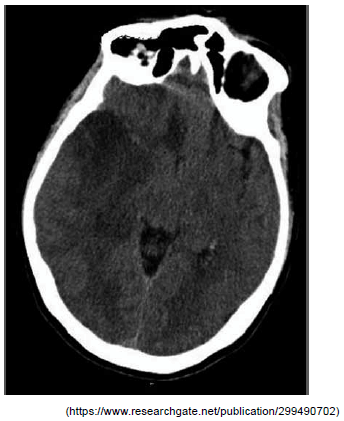

Homem, 51 anos, previamente hígido. Admitido na emergência com queixa de cefaleia bitemporal, pulsátil, início súbito, intensidade moderada e associada a fotofobia e náuseas, com início há cerca de 8 horas. Exame físico: 38,1°C de temperatura corporal, ausência de sinais meníngeos, ausência de sinais neurológicos localizatórios. Durante a observação, evoluiu com agitação psicomotora e confusão mental. Realizada tomografia de crânio sem contraste (a seguir) e coleta de líquor: límpido, pressão inicial 20 mmHg, 3 792 leucócitos, predomínio de mononucleares, glicorraquia normal e proteinorraquia de 120 mg/dL.

Assinale a alternativa que contempla corretamente o diagnóstico desse paciente.